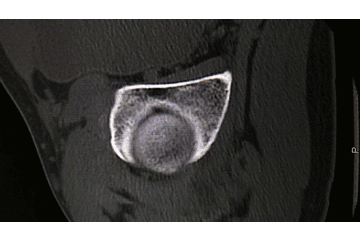

辅助检查:CT 检查提示右侧股骨颈骨皮质不连续,可见透亮骨折线及碎骨片影,断端错位、成角,周围软组织肿胀;右侧髋臼后下缘及左侧耻骨上支骨皮质不连续,断端未见明显错位;右侧髋臼后缘见类圆形稍低密度影,大小约 5*9 mm,边界清楚,边缘见硬化边;右侧髋关节在位,关节间隙未见明显变窄。